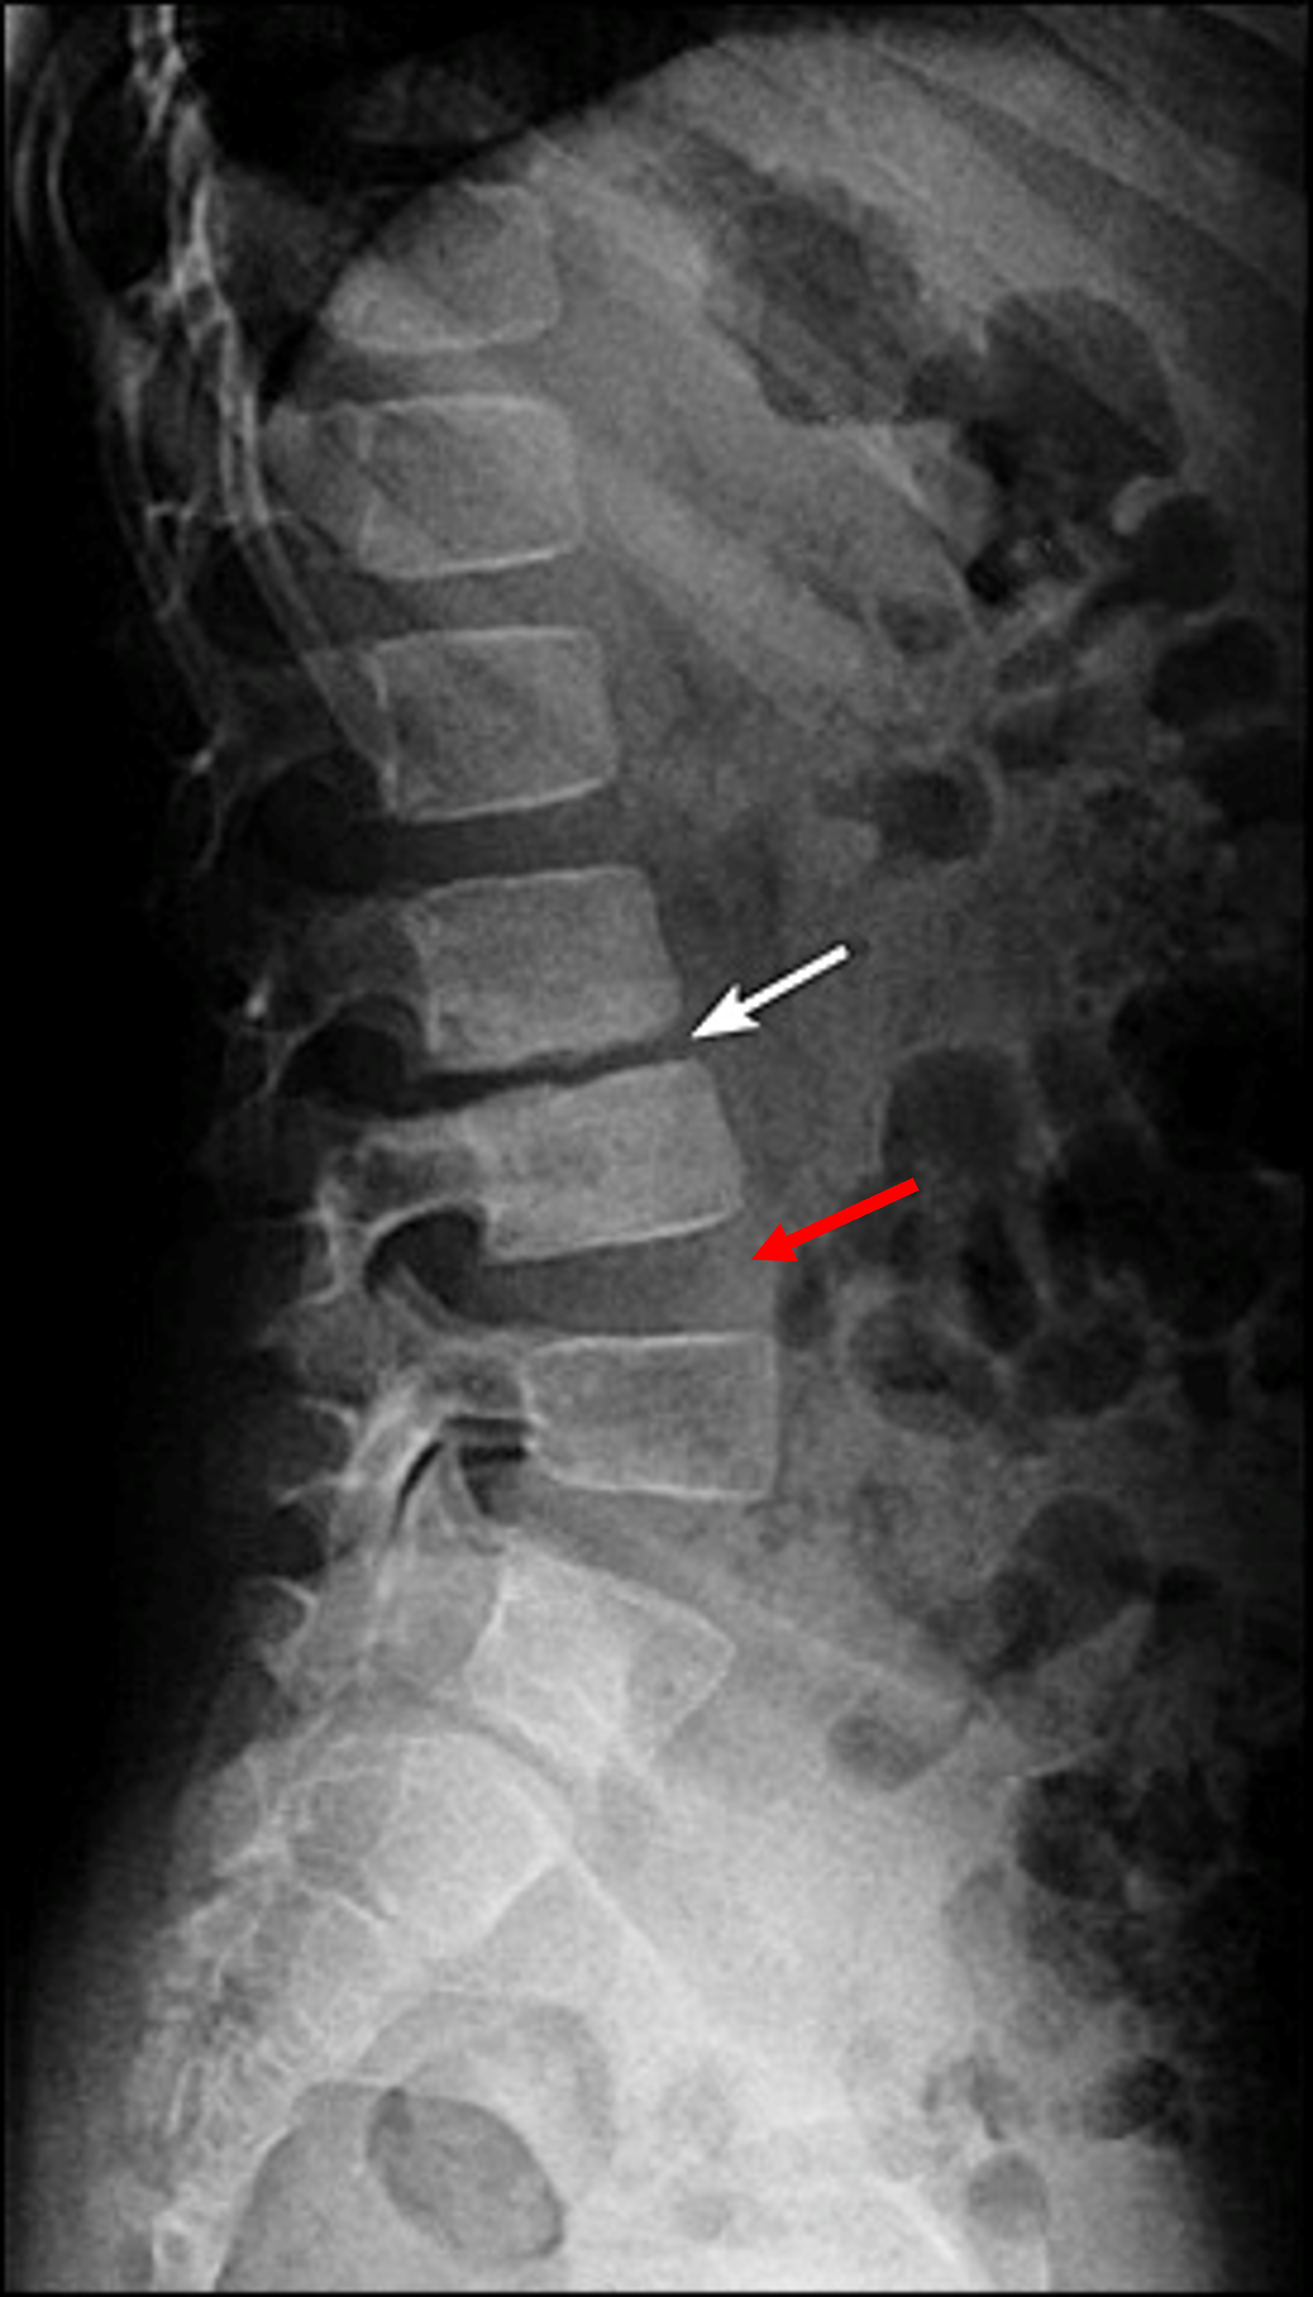

이러한 소견은 염좌에 관한 간접적인 소견에 해당하는데요, 그렇다면 좀 더 심각한 질병을 감별할 수 있는 소견은 무엇일까요? 디스크는 맨 처음 모식도 그림에서 보신 것처럼 척추 뼈 사이사이를 메꾸고 있는 콜라겐 조직입니다. 디스크의 손상은 결국 이러한 콜라겐 조직의 퇴행성 변화를 야기하게 되고, 그 결과 만성 디스크 환자의 경우 손상된 디스크의 높이가, 정상적인 디스크의 높이보다 낮아지게 됩니다.

또한 디스크의 기능 중 하나인 '관절의 안정성'이 무너지기 때문에, 망가진 디스크와 인접한 두 척추 뼈가 불안정하게 흔들리게되고, 이를 보상하기 위해 뼈가 자라나며 두 뼈 사이를 이어주려고 하는, 골극 형성이 일어나는 것도 확인 할 수 있습니다.